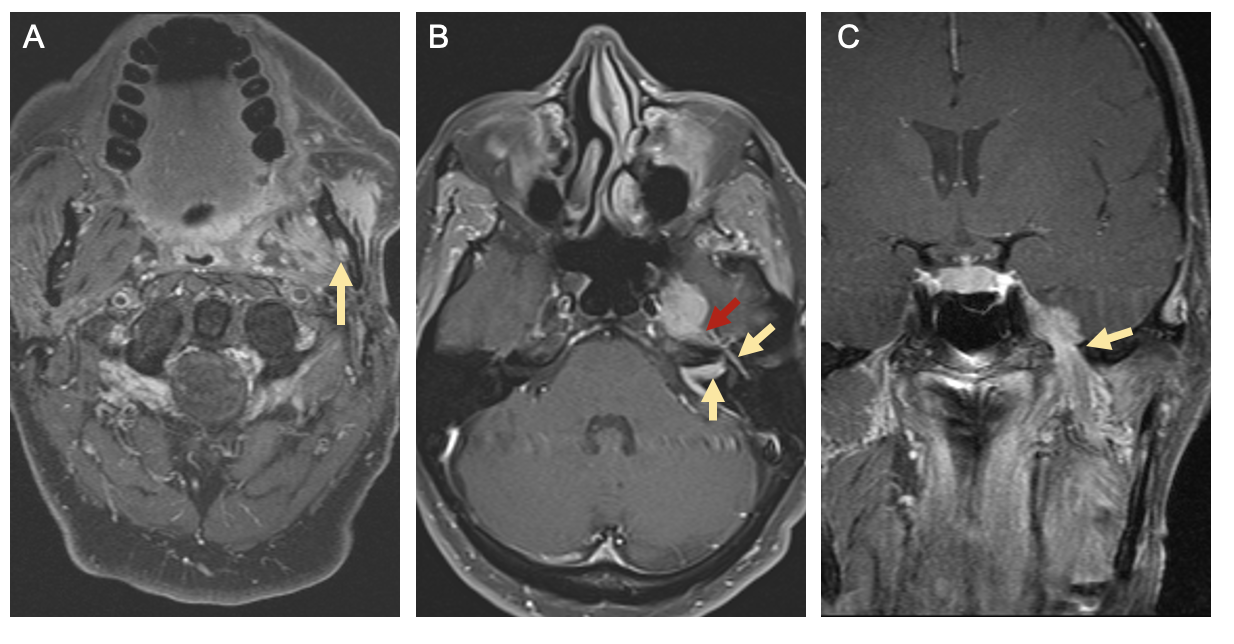

Compared to CT, Magnetic resonance (MR) imaging is better at characterizing soft tissue involvement. As such MRI is the imaging modality of choice for evaluating nerve involvement – with findings such as nerve enlargement and enhancement suggesting PNI – and for better delineating extent of soft tissue invasion [40][41]. CT of the chest with or without contrast or positron emission tomography with 2-deoxy-2-[fluorine-18]fluoro-D-glucose integrated with CT (18F-FDG PET/CT) are tests utilized for detecting distant metastases in patients with advanced nodal disease or identifying primary lung cancers in smokers, both of which have implications for treatment planning [42]. Figure 5 demonstrates radiographic evidence of PNI on MR imaging in a patient with left buccal SCC [1].

Figure 5. Radiographic Signs of Perineural Spread. T1-weighted magnetic resonance (MR) images with gadolinium from a patient with left buccal squamous cell carcinoma and perineural invasion. [A] Axial image showing enlargement and enhancement of the left inferior alveolar canal (yellow arrow). [B] Axial image showing enhancement of the intracanalicular and tympanic segments of the facial nerve (yellow arrows) as well as the greater superficial petrosal nerve (red arrow). [C] Coronal image showing enlargement and tumor involvement of the mandibular branch of the left trigeminal nerve at the foramen ovale (yellow arrow). Reprinted from Misztal CI, Green C, Mei C, et al. Molecular and Cellular Mechanisms of Perineural Invasion in Oral Squamous Cell Carcinoma: Potential Targets for Therapeutic Intervention. Cancers (Basel). 2021;13(23) [1].